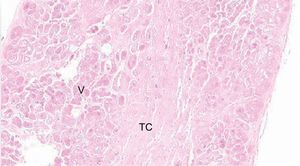

Estudio histológicoDe los 41 corazones estudiados, en 5 de ellos se obtuvieron muestras para histología de los FT. Para ello se conservaron mediante formol, y posteriormente se cortaron y tiñeron mediante hematoxilina-eosina y tricrómico de Masson. Realizamos microfotografías a 10, 20 y 40 aumentos (figura 2).

Resultados del estudio histológicoLa histología de los FT fijados y estudiados muestra fibras musculares y de tejido conectivo en distintas proporciones según la localización del corte. La vascularización de los FT fue evidente en los cortes (figura 5).

Los resultados mediante disección cadavérica de corazones humanos demuestran que la presencia de FT es la norma sin excepción, con una media de entre 3 y 4 FT encontrados. Esta frecuencia es la mayor de las halladas en estudios previos4, ya que en series cortas de animales se había hallado hasta en un 95%16. La histología, como en estudios anteriores, muestra que están compuestos por fibras de colágeno y musculares en distinta proporción, pero son más frecuentes las fibras musculares en los FT de mayor grosor. Esto ha permitido clasificarlos en 2 grupos: musculares y tendinosos, aunque no se sabe si funcionalmente son distintos. Las tinciones realizadas no permitieron visualizar las estructuras de trasmisión eléctrica, si bien hay estudios que refieren su presencia y su implicación en las arritmias cardiacas19,20,26.